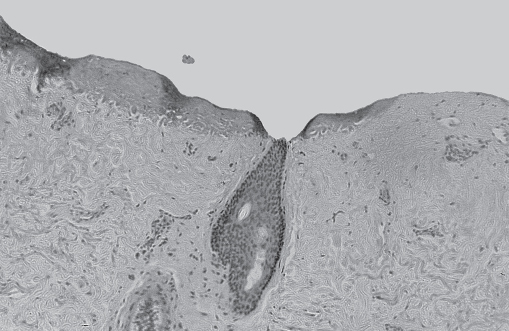

The energy of the initial laser pass is absorbed by the water within the epidermis. Once the dermis has been entered, there is less water to absorb laser energy, and heat transfer contributes to more thermal injury with each successive pass ( Fig. 20.2 ). So ideally, for the CO2 laser, a greater depth of ablation with a smaller number of passes and less thermal injury offers the least risk of scarring. Ultrastructural studies demonstrate smaller collagen fibers within larger collagen bundles in the papillary dermis ( Fig. 20.3 ). After laser resurfacing, wound-healing molecules, such as the glycoprotein tenascin, are expressed as new collagen that is produced in the papillary dermis ( Fig. 20.4 ).